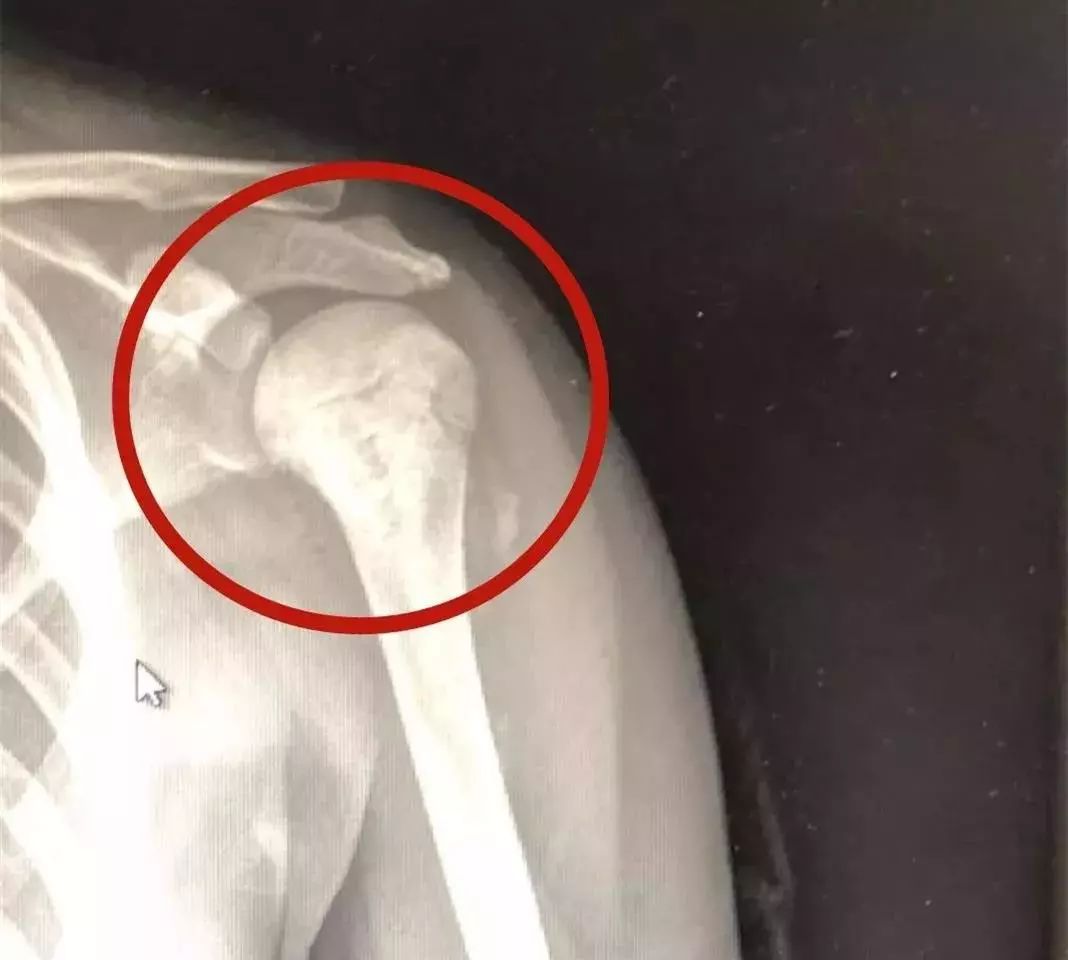

几天过后,小雯发现自己手臂已肿了一圈,静脉都鼓了起来,连书包都背不上,痛得直掉眼泪。全家人连忙将她送到了医院,做了CT及核磁共振检查后,医生怀疑是骨肉瘤,推荐去浙二就诊。得知消息,妈妈像是五雷轰顶,当天便赶到杭州。最终小雯被确诊为骨肉瘤,也就是俗称的骨癌。

(小雯的骨肉瘤)

骨肉瘤是由骨组织的各种细胞发生变异出现“瘤变”,多发生于20岁以下的青少年或儿童,突出症状是肿瘤部位的疼痛,且肿瘤部位距躯干越近,病死率越高。